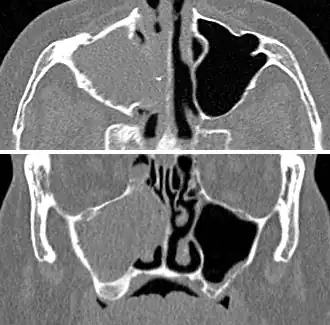

For sinusitis lasting more than 12 weeks, a CT scan is recommended.[66] On a CT scan, acute sinus secretions have a radiodensity of 10 to 25 Hounsfield units (HU). In a more chronic state, they become more viscous, with a radiodensity of 30 to 60 HU.[69]

CT of chronic sinusitis

CT scan of chronic sinusitis, showing a filled right maxillary sinus with sclerotic thickened bone